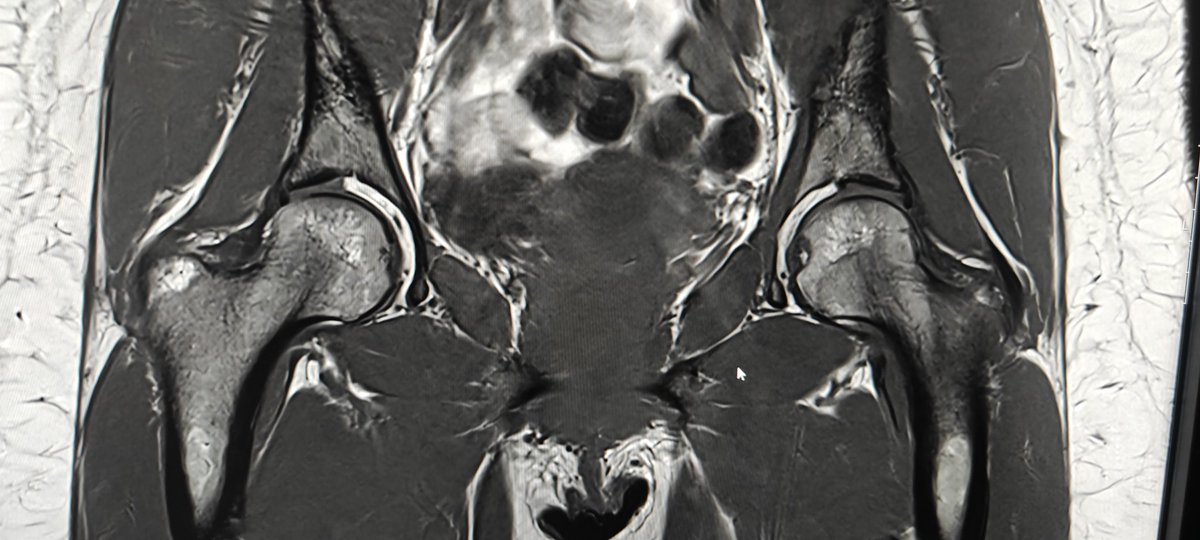

I've probably walked past this loads of times but the paucity of cartilage covering in both hips on the acetabular side 🤔 Almost certainly variant anatomy and not pathological but striking. Chondral efficiency 😁 #mskradiology #mskrad

Neeraj Purohit tweet mediaNeeraj Purohit tweet media